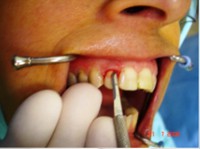

Carga Imediata após exodontia atraumática

Fatos interessantes pertinentes a este caso:

- Extração imediata

- Implante imediato

- Carga imediata

- Coroa protética cerâmica imediata

- Aplicação da cerâmica de baixa fusão direto sobre o pilar